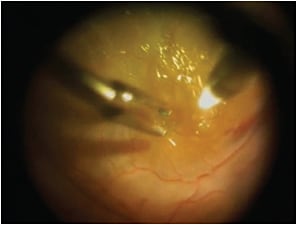

The study was further categorized with regard to PVR stage. Grade A PVR was defined as vitreous haze or vitreous pigment clumping, while Grade B PVR included wrinkling of the inner retinal surface, a rolled edge of a retinal break, or retinal stiffness (Figure 1, page 32). A full-thickness retinal fold, or a star fold in one area, was considered to be Grade C-1 PVR (Figure 2, page 32). PVR ranged from Grade 0 (no PVR) to Grade C-1, and all of the patients had at least three months of follow-up. To our knowledge, this was the largest study of patients with RRD: 181 surgeons from 48 countries provided information on 7,678 RRDs. Most of the results from this study group have already been published.1-4

Figure 1. Intraoperative view with a BIOM of PVR B retinal detachment.